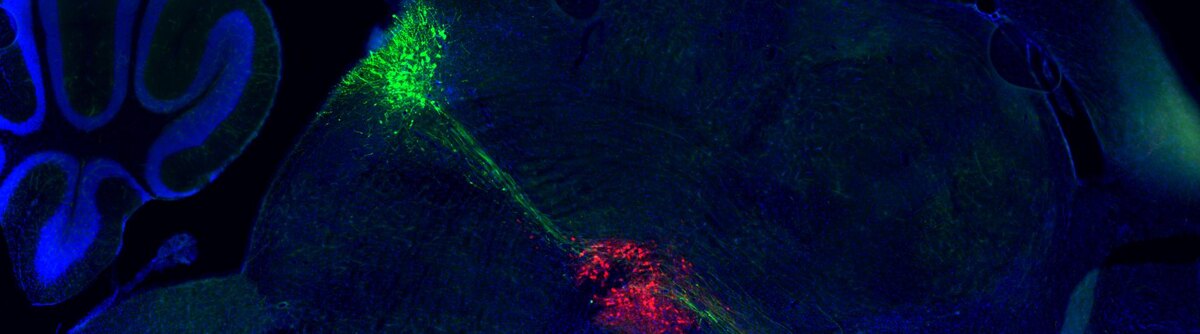

Исследовательской группой под руководством аспиранта Даниэля Кардозо Пинто была выведена особая линия мышей, которая позволяла им одновременно наблюдать и контролировать как дофаминовую, так и серотониновую систему в организме животных.

Этот инновационный подход помог им точно установить область мозга, где эти системы взаимодействуют друг с другом, а именно — в лимбической области под названием nucleus accumbens (центр удовольствия — прим. перев.), играющей ключевую роль в обработке эмоций, мотивации и поощрения.

Затем учёные использовали оптогенетическое манипулирование (метод, где для контроля генетически модифицированных нейронов используется свет), чтобы во время дрессировки избирательно глушить нормальный сигнал каждой из систем, либо по одной, либо в комбинации.